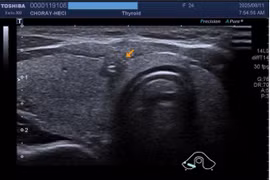

Bệnh viện Bãi Cháy (Quảng Ninh) đã phẫu thuật thành công cho trẻ 12 tuổi mắc ung thư tuyến giáp di căn hạch cổ. Đây là trường hợp bệnh nhân ung thư tuyến giáp trẻ tuổi nhất từng được phẫu thuật điều trị tại bệnh viện.